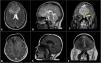

El compromiso del sistema nervioso central por mieloma múltiple es infrecuente y se diagnostica en menos del 1% de los casos. El diagnóstico diferencial incluye linfomas, metástasis, sarcomas, osteocondromas, hemangiopericitomas o meningiomas. Se presenta el caso de una paciente femenina de 46años con antecedentes de mieloma múltiple en remisión posterior a trasplante de médula ósea que consulta por masa palpable en la región frontal, cefalea holocraneana intensa y disminución de la agudeza visual de dos meses de evolución con imágenes compatibles con meningioma del surco olfatorio.

Se realiza craneotomía y resección total de lesión por abordaje bicoronal. El análisis histopatológico reveló una proliferación neoplásica con células de núcleo esférico y citoplasma eosinófilo lateralizado, compatible con compromiso del sistema nervioso central por mieloma múltiple. Esta patología ofrece retos en el diagnostico imagenológico preoperatorio por las grandes similitudes con otras neoplasias, principalmente los meningiomas, por lo que es importante considerarlo como diagnóstico diferencial.

Central nervous system involvement by multiple myeloma is extremely rare and is diagnosed in less than 1% of cases. Differential diagnosis includes lymphomas, metastases, sarcomas, osteochondromas, hemangiopericytomas or meningiomas. We report a 46-year-old female with a history of multiple myeloma in apparent remission after autologous bone marrow transplantation, who consulted for a palpable mass in the frontal region associated with holocranial headache and decreased visual acuity of two months of evolution with imaging studies compatible with olfactory sulcus meningioma.

A craniotomy and total resection of the lesion by bicoronal approach was performed and histological sections showed a neoplastic proliferation consisting of cells with a spherical nucleus and lateralized eosinophilic cytoplasm. Lesion compatible with involvement of the central nervous system by multiple myeloma. This case highlights the diagnostic challenge due to radiologic similarity with other tumors, especially meningiomas, and emphasizes including myeloma in differential diagnoses.